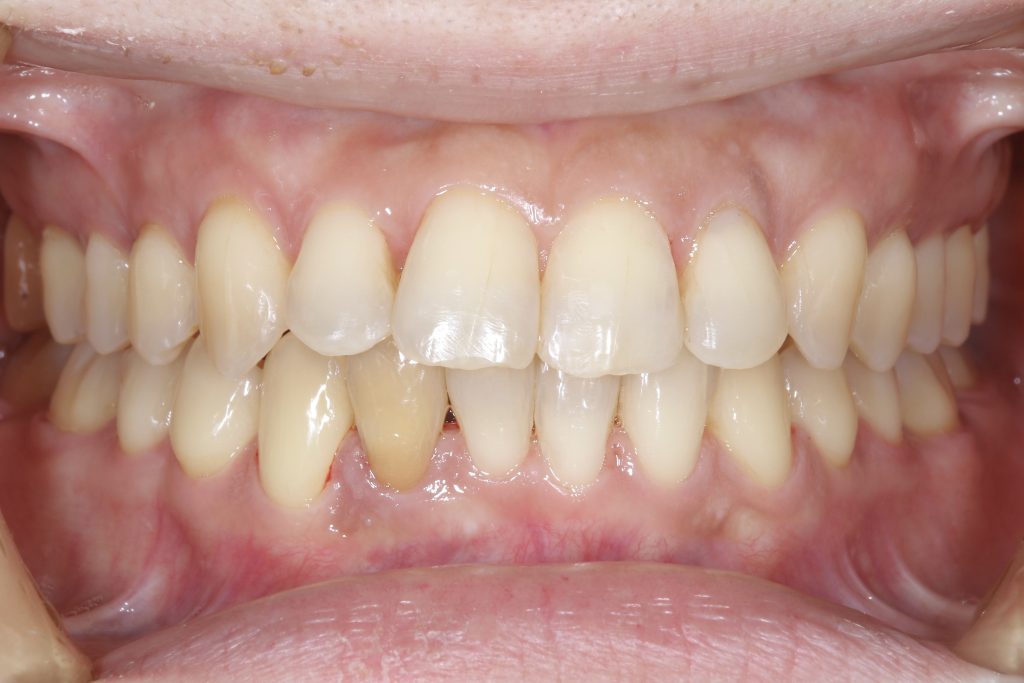

受け口の状態により、上の歯が内側に入り込み、反対の噛み合わせになっている部分が見られました。見た目の問題だけでなく、噛み合わせのバランスにも影響を与えていました。

- 前歯部交叉咬合を伴う不正咬合

- ゴムメタルワイヤー矯正

- 2024年9月6日(10ヶ月)

- 約90万円(税込)